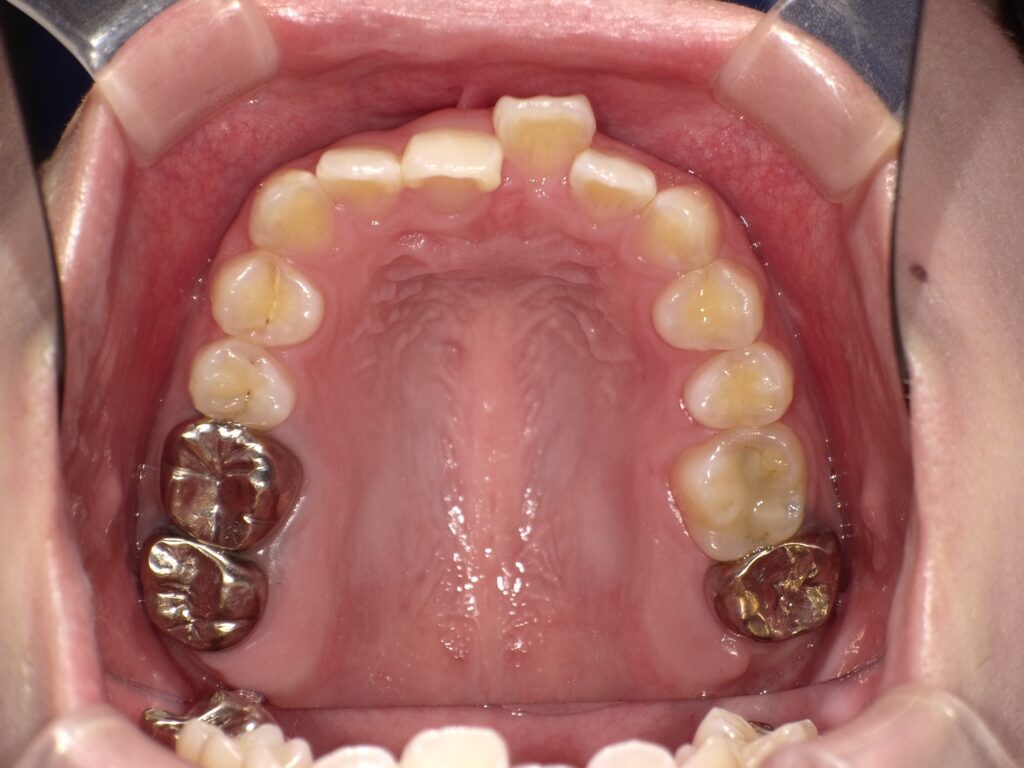

このように、上下どちらか一方だけ歯並びが悪いというお悩みは意外と多く見られます。

この記事では、上だけ/下だけ歯並びが悪くなる原因や放置したときのリスク、矯正の考え方について解説します。